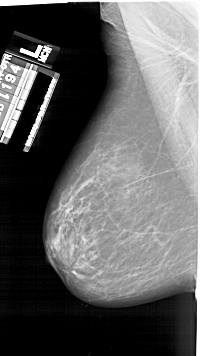

A_1925_1.RIGHT_MLO

RIGHT_MLO LINES 6241 PIXELS_PER_LINE 3496 BITS_PER_PIXEL 12 RESOLUTION 43.5 OVERLAY